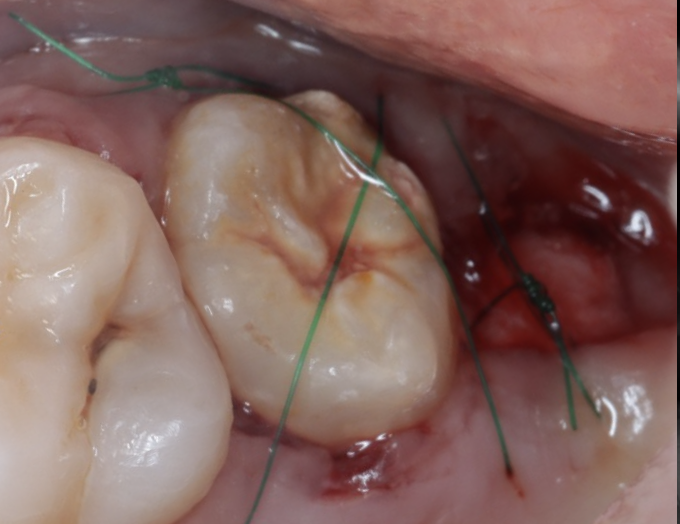

4)移植床形成 → ドナー歯抜歯 → 移植

口腔外時間や試適回数を最小化し、歯根膜ダメージを抑えることを最優先に進めます。

5)固定・咬合調整・経過観察

初期治癒を安定させ、必要なら追加治療(根管治療、最終補綴、歯周管理)へ。